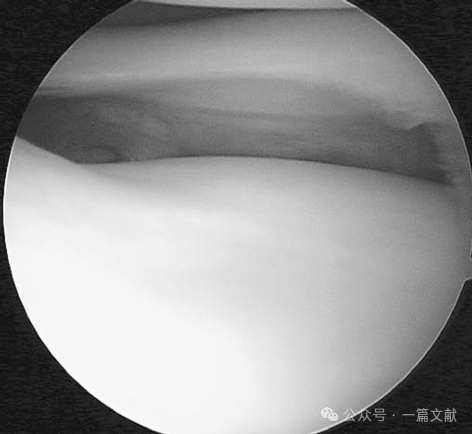

8.膝关节中1/3外侧关节囊韧带:该韧带是膝关节外侧囊的局部增厚结构,其解剖学意义相当于膝关节内侧的深部内侧副韧带。本质上,它是由附着于股骨并向下延伸至胫骨外侧的关节囊构成。其股骨前侧附着线起自外上髁前上方,向后延伸至股骨外侧髁上髁突后缘。在这条细长的囊性附着线上,它与股骨腘肌附着点的后部相连,并向后走行,最终止于股骨腓肠肌外侧头肌腱附着处。

左膝中1/3外侧关节囊韧带(已切开,箭头所示)。浅层髂胫束已被牵开,后方可见腓侧副韧带(FCL)